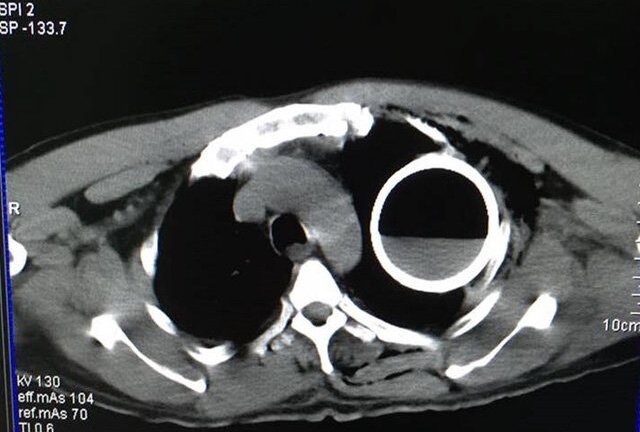

Bệnh nhân ngã cầu thang, bị một dị vật chưa xác định đâm vào vùng lõm xương đòn và mắc trong ngực, gây khó thở; sau khi chụp X quang và CT, các bác sĩ ngỡ ngàng khi thấy một vỏ chai thuỷ tinh còn nguyên vẹn trong lồng ngực bệnh nhân.